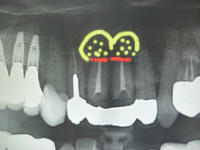

今日のオペは上顎左右1番の歯根端切除と骨補填です。

この部位の根尖には歯冠大の歯根嚢胞があり、ずっと根管治療を行ってきたのですが、根尖からの排膿が消失せずなかなか良くならなかった為に、歯根嚢胞と感染した根尖部を根こそぎ除去してしまう歯根端切除術,及び骨補填する術式を選択することになった次第です。